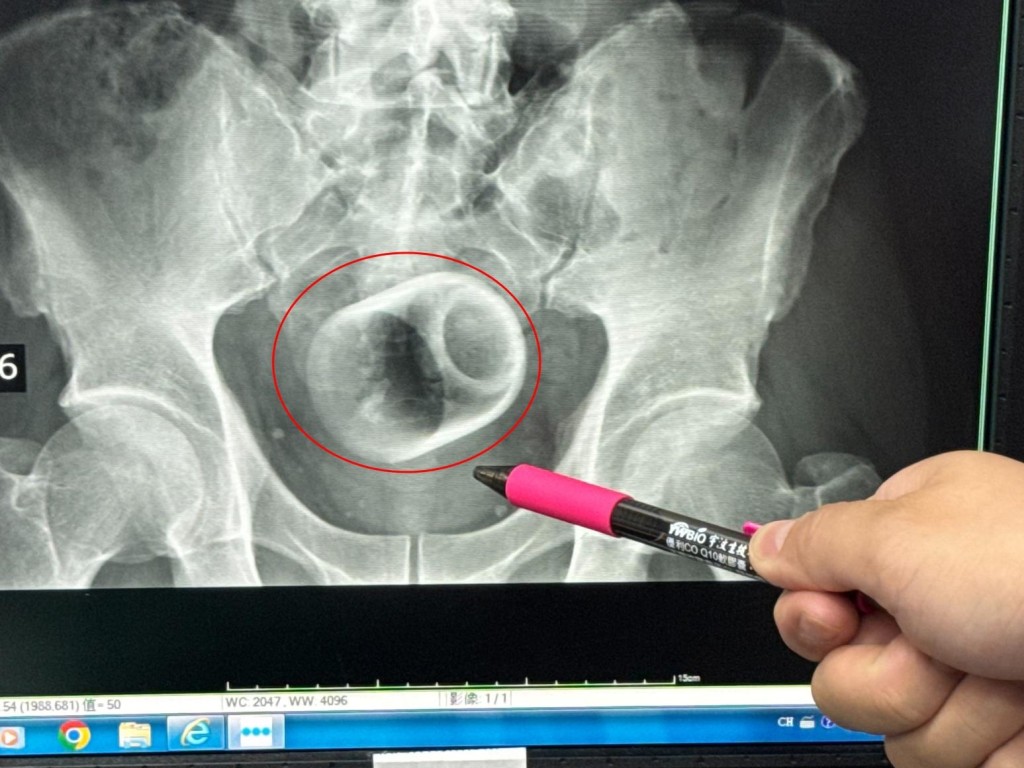

據「中時新聞網」,吳坤達表示,該名患者到院時稱,已經3天無法大便很困擾,害羞不敢提及自己肛門塞了一個杯子,經過X光攝影檢查,可見骨盆腔內有一個直徑約6cm、高約8cm的杯子,杯口朝下,自己當時見狀嚇一大跳,立即安排進手術室,要把杯子拿出來。

X光攝影檢查,可見骨盆腔內有一個杯。 李綜合醫院

吳坤達說,起初使用器械要把杯子夾出來,但因杯子光滑無法施力,加上杯身全被大腸包住,部分腸子缺血也造成壞死,後來再使用腹腔鏡,依舊無法順利取出,也擔心把杯子夾碎,傷及患者或造成感染風險,最後只好在肚子上動刀劃開腸子,手術總共歷經2個多小時,最終才取出杯子,同時做好一個人工造口,讓患者能夠暫時排便。